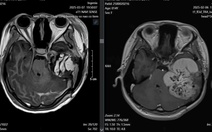

Tại đây, kết quả chụp cộng hưởng từ (MRI bụng có tiêm thuốc) cho thấy gan to, xơ hóa, ngấm thuốc không đồng đều ở thì tĩnh mạch; tĩnh mạch gan giãn, hẹp đoạn đổ vào tĩnh mạch chủ dưới. Tuần hoàn bàng hệ vùng thượng vị phát triển rõ, lách to (143mm), thành túi mật dày. Không ghi nhận huyết khối lớn hay dịch ổ bụng tự do.

Hình ảnh gợi ý hội chứng Budd-Chiari, một tình trạng hiếm gặp do tắc nghẽn dòng chảy máu ra khỏi gan, thường là do cục máu đông (huyết khối) làm hẹp hoặc tắc nghẽn các tĩnh mạch gan hoặc tĩnh mạch chủ dưới.